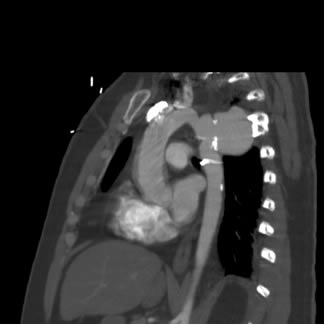

The patient is a 33 year old male with a history of juxtaductal coarctation who underwent a repair early in infancy. The patient had a recurrence of the coarctation and underwent a second open repair and left diaphragm plication at 2 years of age. He was lost to follow-up until recently when he presented to an emergency room with a several week history of hemoptysis and left back pain. The patient’s physical exam was remarkable only for a well-healed left thoracotomy incision. The patient was afebrile with equal blood pressures in all 4 extremities. The patient’s white count was normal. A CT scan of the chest demonstrated a saccular aneurysm of the proximal descending thoracic aorta measuring approximately 6cm in diameter (Figure 1). The patient was transferred to the Oregon Health and Sciences University for further management.

At our institution a dedicated CT angiogram of the chest was obtained to better define the morphology of the patient’s arch and aneurysm. This confirmed the finding of a saccular aneurysm just distal to the left subclavian artery takeoff. Because of the patient’s prior history of coarctation recurrence and repair, this was felt most likely to represent a pseudoaneurysm, possibly at the site of a patch repair. Aortic reconstructions of the CT angiogram showed no evidence for recurrence of the coarctation (Figure 2). There was, however, a size discrepancy in the diameter of the aorta above and below the aneurysm. The diameter of the aortic arch between the left carotid and left subclavian arteries was 13mm. The diameter of the descending thoracic aorta distal to the aneurysm was 23mm.